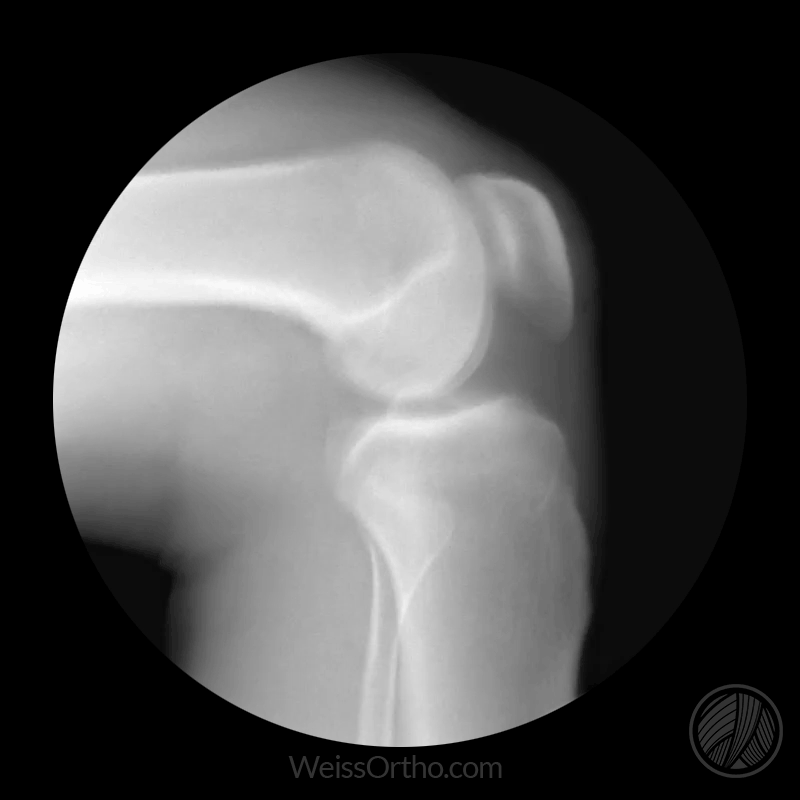

Aquela dor constante nas articulações, a rigidez ao levantar da cama, o inchaço nos joelhos ou a sensação de travamento ao caminhar não são normais.

É o sinal claro de que suas articulações estão inflamadas, desgastadas e precisando de suporte imediato para evitar a progressão do problema.